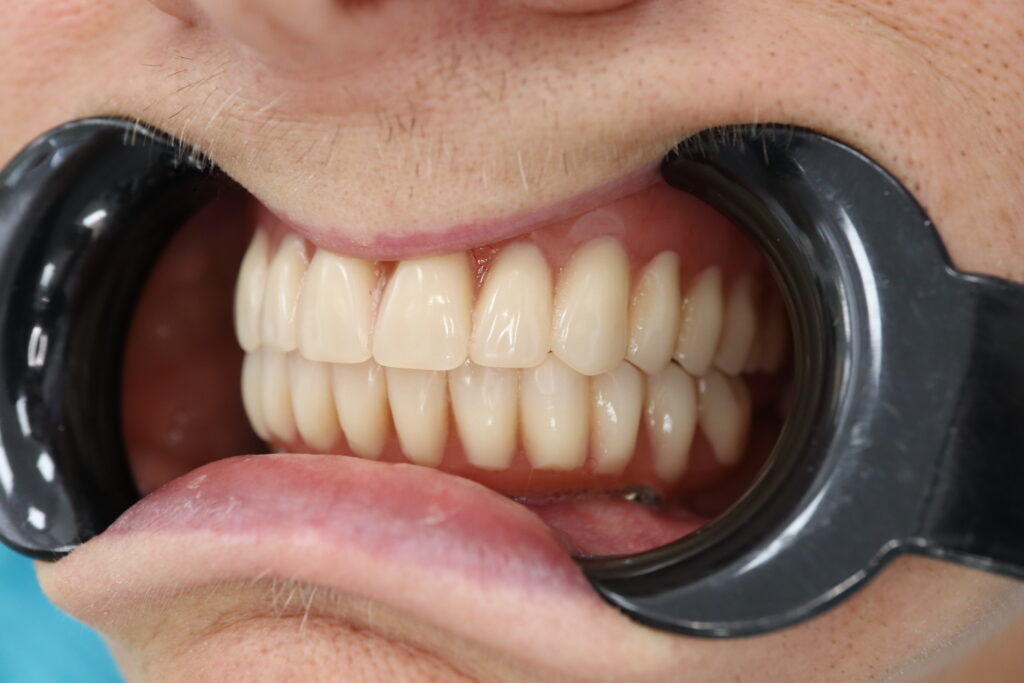

Спустя 7 дней на нижней челюсти зафиксирован металлоакриловый протез из 12 зубов с опорой на 4 дентальных имплантата.

На верхнюю челюсть изготовлен съемный акриловый протез.

результат